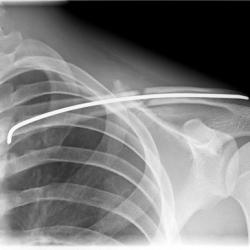

Röntgenbilder

• Schlüsselbeinbrüche

• Schultereckgelenksverletzungen/-sprengungen